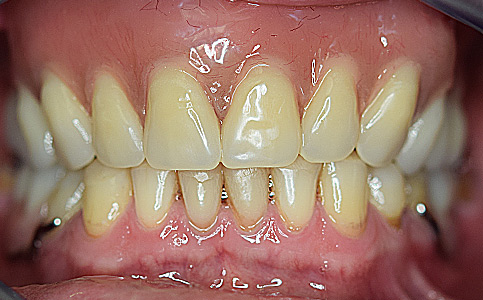

Pacjent zgłosił się do naszej kliniki ponieważ marzył o pięknym uśmiechu. Jego metamorfoza była wielospecjalistyczna. Pierwszym etapem było leczenie biologiczne, następnie uzupełnienie braków zębowych implantami oraz wykonanie koron pełnoceramicznych na zęby górne. Dzięki temu Pacjent odzyskał pewność siebie i zdrowy uśmiech.